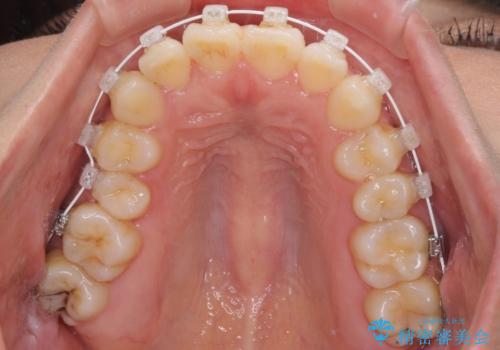

- 審美装置

受け口傾向の非抜歯矯正であったため、インビザラインによる矯正治療をお勧めしましたが、自己管理が面倒であるとのことで、ワイヤー装置にて行うこととしました。

なお、右奥の歯が180度回転した状態で萌出しており、こちらは改善困難なため、そのままの向きで配列することとしました。

右奥の歯が180度回転していることで、噛む度にワイヤーに無理な力がかかったようで、頻繁にワイヤーが切れてしまいました。また、下顎を後方に移動させるためのアンカースクリューも脱離することが多く、治療期間が長くなってしまいました。